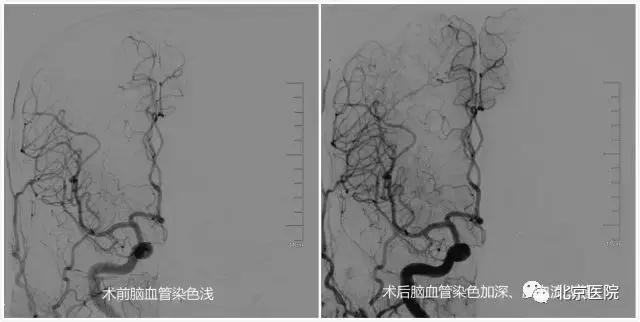

日前,一位88岁老人家属发来的短信让北京医院神经外科的全体医护人员倍感欣喜。原来,这位老人在春节前因“突发左侧肢体瘫痪”在我院确诊为“急性脑梗死”和“颈动脉重度狭窄”,家人告诉医生,老人几年前就因“记性不好、整天瞌睡”在其他医院诊断了“老年痴呆”,现在已“生活自理困难”。在完善相关准备后,我院神经外科为其实施了“微创”的颈动脉狭窄支架成形术。术后老人一改之前的“萎靡不振”,竟然“兴致勃勃”地与旁人聊起了家常,第二天就要求出院回家过春节去……这不,春暖花开,老人特意嘱托家属发来短信,感谢北京医院神经外科医护人员帮他度过了一个健康快乐的春节。

针对颈动脉狭窄,早在上世纪90年代,北京医院神经外科刘树山主任就开展了颈动脉内膜剥脱术;2002年,在国内最早报道了采用脑保护装置辅助进行颈动脉狭窄支架成形术。神经外科还与神经内科、放射科、超声医学科、核医学科等兄弟科室开展长期合作,围绕颈动脉狭窄患者的认知功能、脑血流灌注、颈动脉斑块稳定性等热点和难点问题,进行了深入的临床和基础研究;先后承担了原国家卫生部临床学科重点项目、首发基金项目、北京医院“121项目”等多项科研课题;发表相关学术论文30余篇;主办了大型脑血管病研讨会10余次。值得一提的是,作为国家老年医学中心,北京医院接诊的颈动脉狭窄患者一直以老年、高龄患者居多,仅在2016年,就治疗了老年颈动脉狭窄患者74例(占总数70%多),无一例出现严重手术并发症。